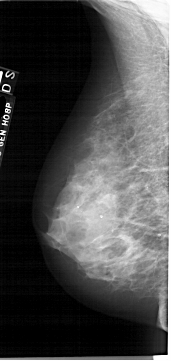

A_1877_1.RIGHT_CC

RIGHT_CC LINES 4966 PIXELS_PER_LINE 2701 BITS_PER_PIXEL 12 RESOLUTION 43.5 OVERLAY